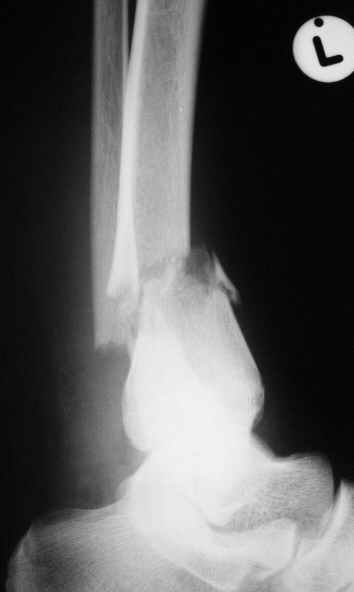

Уважаемый Виталий Евгеньевич,

Помятуя наш недавний разговор о фиксации м.б. кост, высылаю послеоперационные картинки..

Напомню- разбирали случай 17 летнего молодого человека перелом дист тиб.фиб. хирургия после 3 недель с момента травмы( безуспешные попытки закрытой репозиции) Раны заживают первичным натяжением, занимается физиотерапией, пока никаких проблем не наблюдается

Как ты тут оцениваешь восстановление оси большеберцовой кости?

Является ли рутинной практикой у вас использовать снимок противоположной конечности как шаблон для измерения осевых отклонений?

Согласный я с тобой:-)) есть остаточная вальгусная деформация (по снимку видно перекрывание дист. фрагментом б.б по латеральной поверхности проксимальноо фагмента на 2-3 мм и наружная лодыжка репонирована с укорочением, судя по прямой проекции. Необходимость использования интраоперационно дистрактора была бы оправдана (вручную было непросто *вытянуть* дистальный отломок.)

> Является ли рутинной практикой у вас использовать снимок

> противоположной конечности как шаблон для измерения осевых

> отклонений?

Нет, рутинным не назовешь, в данном случае отклонение оси видно и невооруженным взглядом без сравнения со здоровой стороной. Сравнительную осевую оценку со здоровой стороной использую только при планировании коррегирующих остеотомий.

На мой взгляд, Ваша демонстрация неожиданно добавила перцу. Если память мне не изменяет, я говорил об отсутствии показаний к остеосинтезу малоберцовой.

Сейчас можно заикнуться о вредности этой манипуляции с точки зрения риска фиксации в неправильном положении, как это получилось у Вашего пациента. Сначала фиксировали большеберцовую, и надо было на этом остановиться, ин май хамбл опиньон. Потом при закручивании винтов на мощнейшей второй пластине сустав увело на вальгус. С учетом того, что пацану всего 17, я бы удалил пластину с малоберцовой и попытался тем или иным способом устранить смещение, пока не срослось.

Извините, если что не так,

Все так и не совсем - последовательность процедуры( я уже, кажется, упоминал)открыл зону перелома б.б., оценил мобильность фрагментов при очевидном смещении - отрепонировать вручную не получилось и понятна причина. Открыл область перелома м.б. отрепонировал( как мне показалось вполне адекватно) и фиксировал пластиной. ПРи ревизии зоны перелома б.б. положение фрагментов улучшилось, но сохранялось остаточное смещение дистального фрагмента кпереди хоть и незначительное, которое устранил и фиксировал межфрагментарным винтом, далее пластина. Конечно, следовало интраоперационно проконтролировать РГ, откровенно говоря, не ожидал, что постоп контроль будет так выглядить, показалось , что достигнутая репозиция вполне адекватна.....

Согласен с вашей рекомендацией (пока парень отпросился на выходные домой, а по возвращении будет разговор) Кстати ваш аргумент в пользу важности адекватной репозиции м.б. .... Поскольку оставшийся вальгус ничем , кроме, как укорочением м.б не объяснить - для ревизии приготовлю дистрактор.